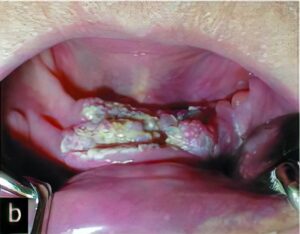

悪性腫瘍

口腔内に発生する悪性腫瘍では、扁平上皮癌という口腔内の粘膜から発生する癌が最も多いのが特徴です。その他には、唾液腺から発生するものや骨肉腫などの内部の組織から発生する悪性腫瘍もあります。

悪性腫瘍を歯周病や口内炎、義歯による傷などと思い込み、長期間放置し、腫瘍が大きくなてから歯科医院を受診するケースが多いようです。口腔内の悪性腫瘍だけに限定される話ではありませんが、早期発見・早期治療が重要です。